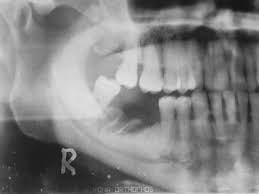

Profilaxis de la osteonecrosis de la mandíbula relacionada con la medicación: Un ensayos controlados aleatorizados (ECA)  abierto proporcionó algunas pruebas de que los exámenes dentales en intervalos de tres meses y los tratamientos preventivos pueden ser más efectivos que la atención estándar para reducir la incidencia de la osteonecrosis de la mandíbula relacionada con la medicación (OMRM) en personas que toman bisfosfonatos intravenosos para el cáncer avanzado. La certeza de la evidencia se consideró muy baja. No hay pruebas suficientes para reclamar o refutar un beneficio de las intervenciones probadas para la profilaxis de la OMRM en pacientes con tratamiento antirresortivo sometidos a cirugía dentoalveolar. Aunque algunas intervenciones sugirieron un gran efecto potencial, los estudios no tuvieron suficiente poder estadístico para mostrar significación estadística y está pendiente la replicación de los resultados en estudios más amplios.  Tratamiento de la osteonecrosis de la mandíbula relacionada con la medicación: Las pruebas disponibles son insuficientes para reclamar o refutar un beneficio, además de la atención estándar, de cualquiera de las intervenciones estudiadas para el tratamiento de la OMRM. Cochrane Database Syst Rev. 22 de julio de 2022

Este estudio contribuye a la escasa pero creciente literatura que asocia un número creciente de fármacos con osteonecrosis de la mandíbula relacionada con la medicación (ONMRM)  y subraya la importancia de considerar todos los fármacos posibles que elevan el riesgo de ONMRM de un paciente. Br J Clin Pharmacol, junio de 2021